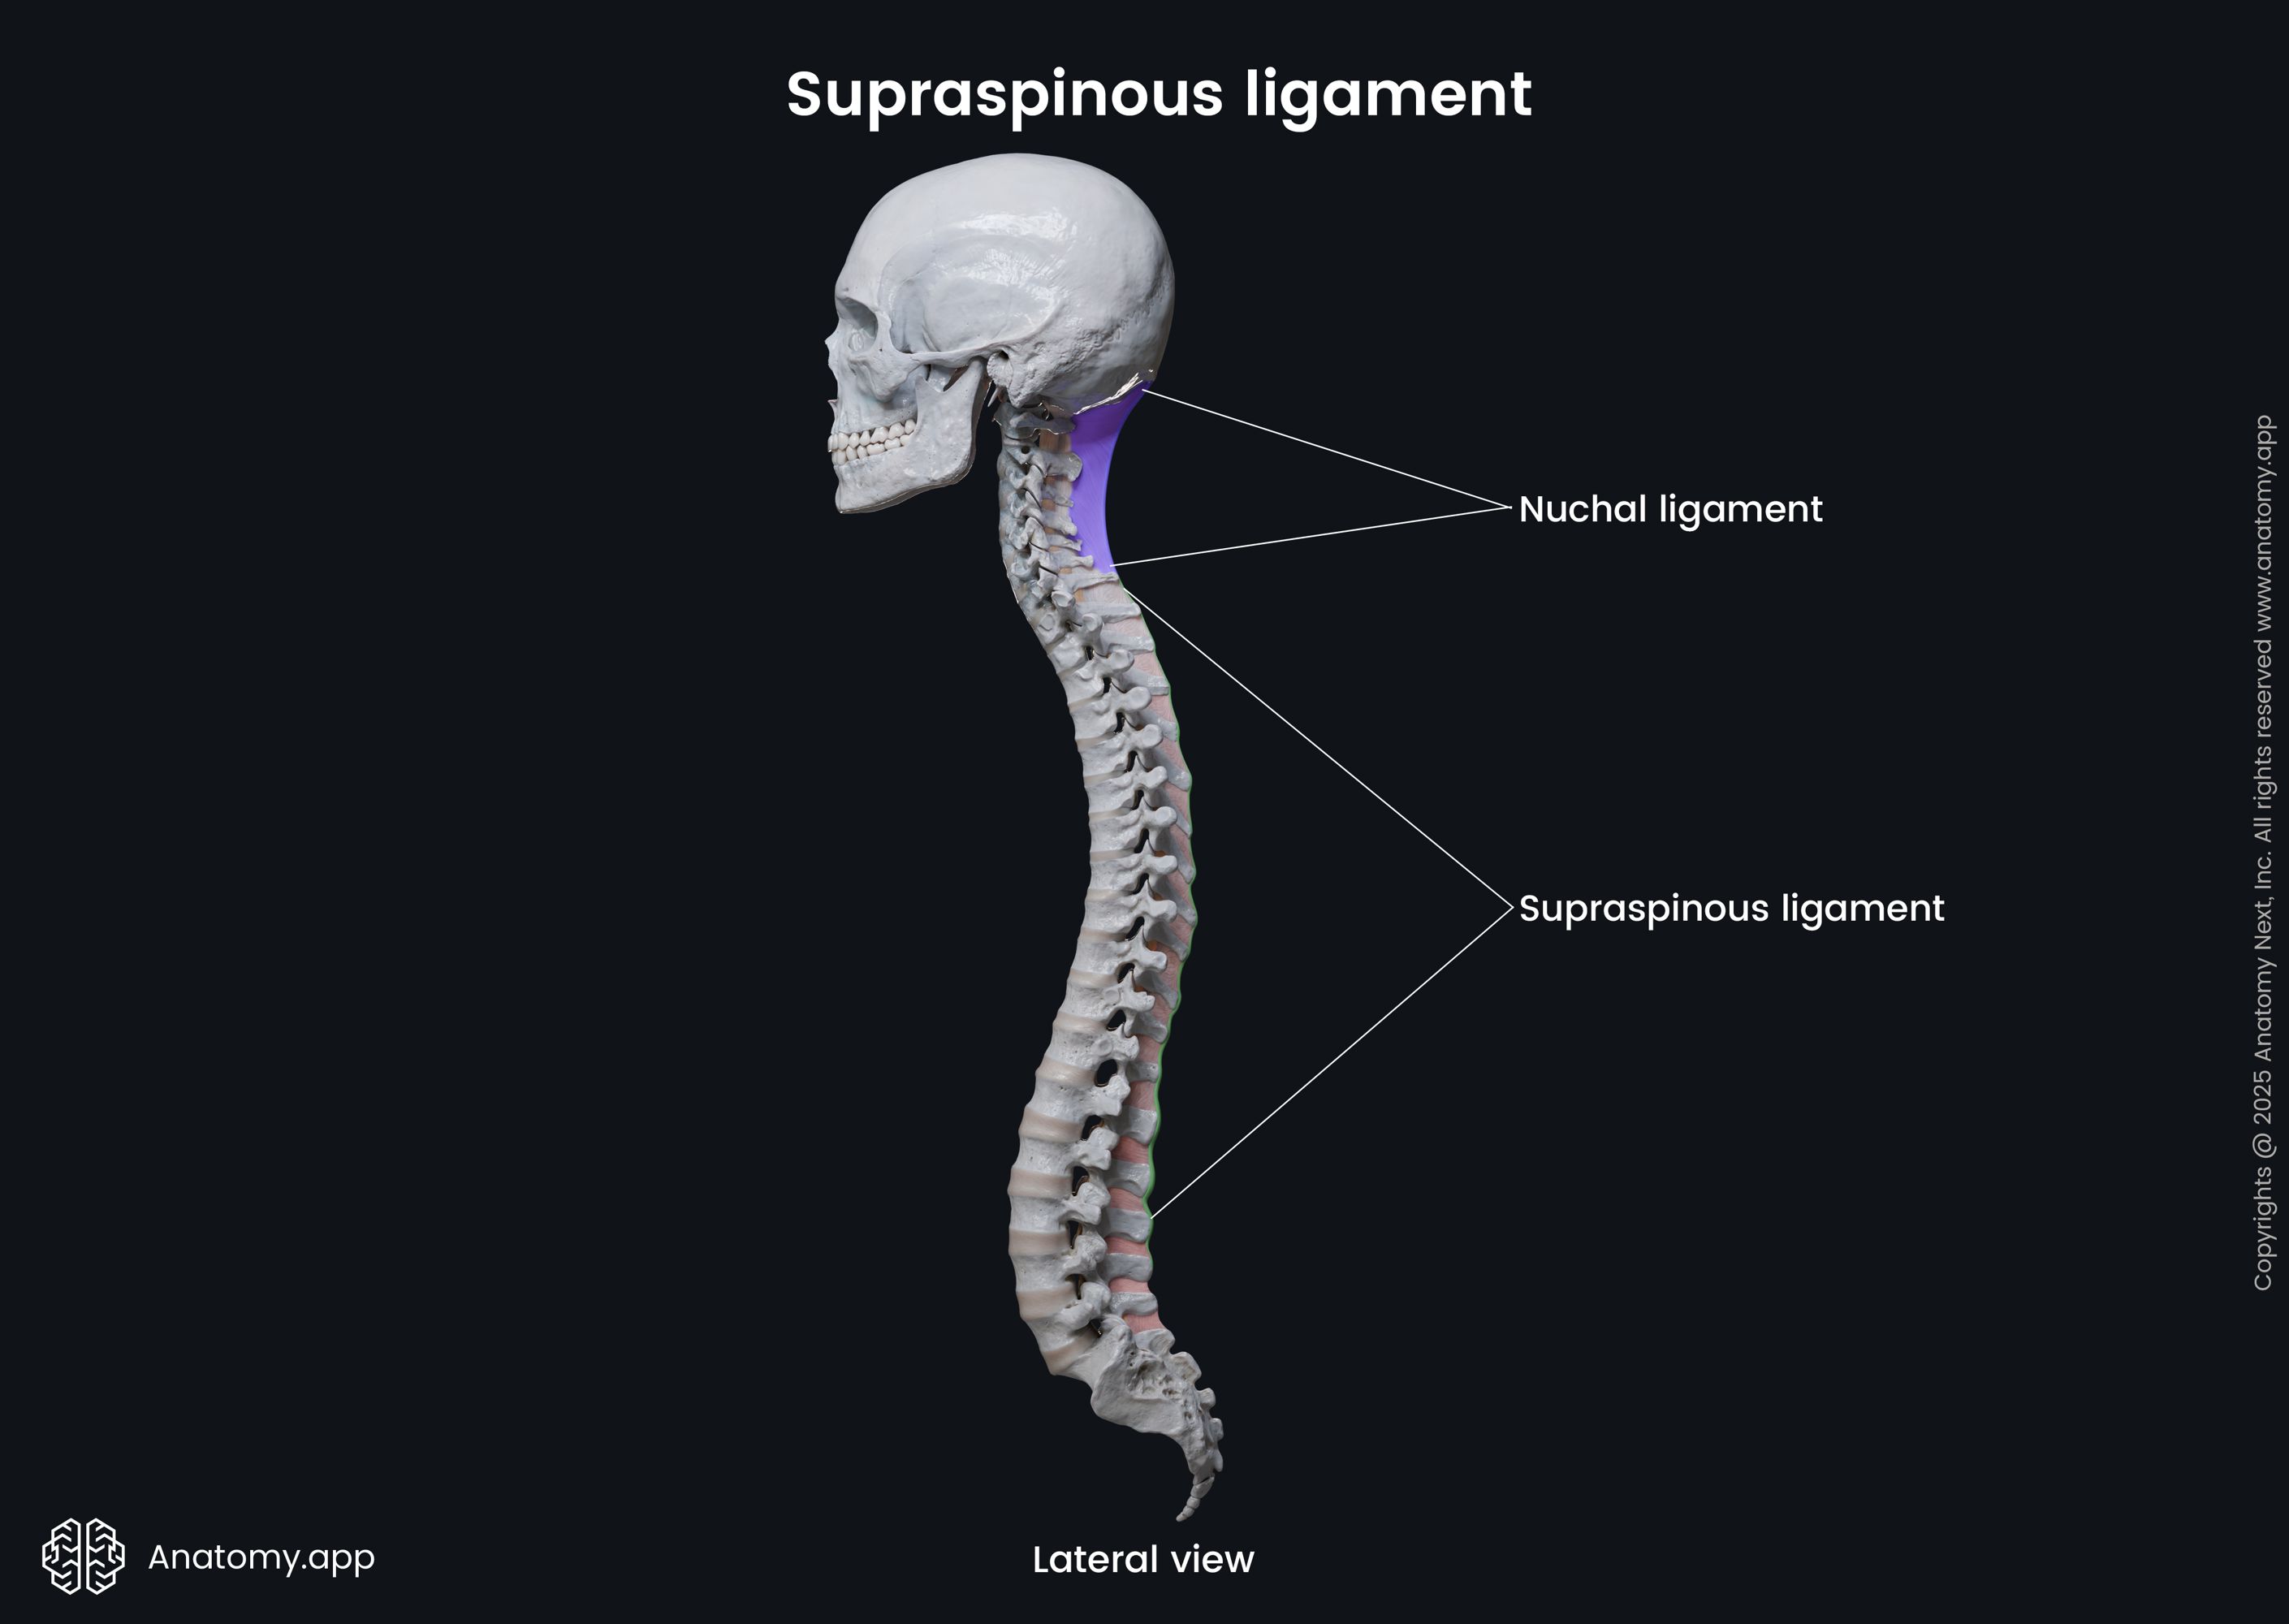

Pure Health - Anatomy 101 - Supraspinous ligament and interspinous ligament 📚 The supraspinous ligament and interspinous ligament work together to limit flexion of the spine by limiting separation of the spinous

Afraid to stick your neck out when it comes to naming cervical spine ligaments? Know the anterior longitudinal ligament (ALL) \u0026 that's ALL? Is the nuchal ligament a NEW CALL for you?